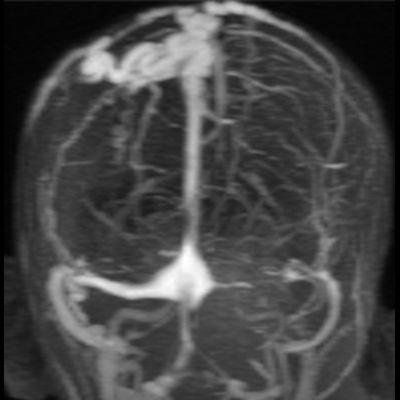

2. B) Kontrastlı MR venografide orta hatta cilt altı dilate (oklar), tortiyoze emisserian vaskuler yapıların superior sagital sinus ile ilişkisi ve devamlılığı (ok) izlenmektedir.

6. En tanımlayıcı görüntüleme yöntemi MR venografidir.

7. İntrakraniyal ve ekstrakraniyal venöz yapıların ilişkisi net şekilde gösterilir.

8. Lezyonun süperior sagittal sinüs veya diğer venöz sinüslerle bağlantısı doğrulanır.